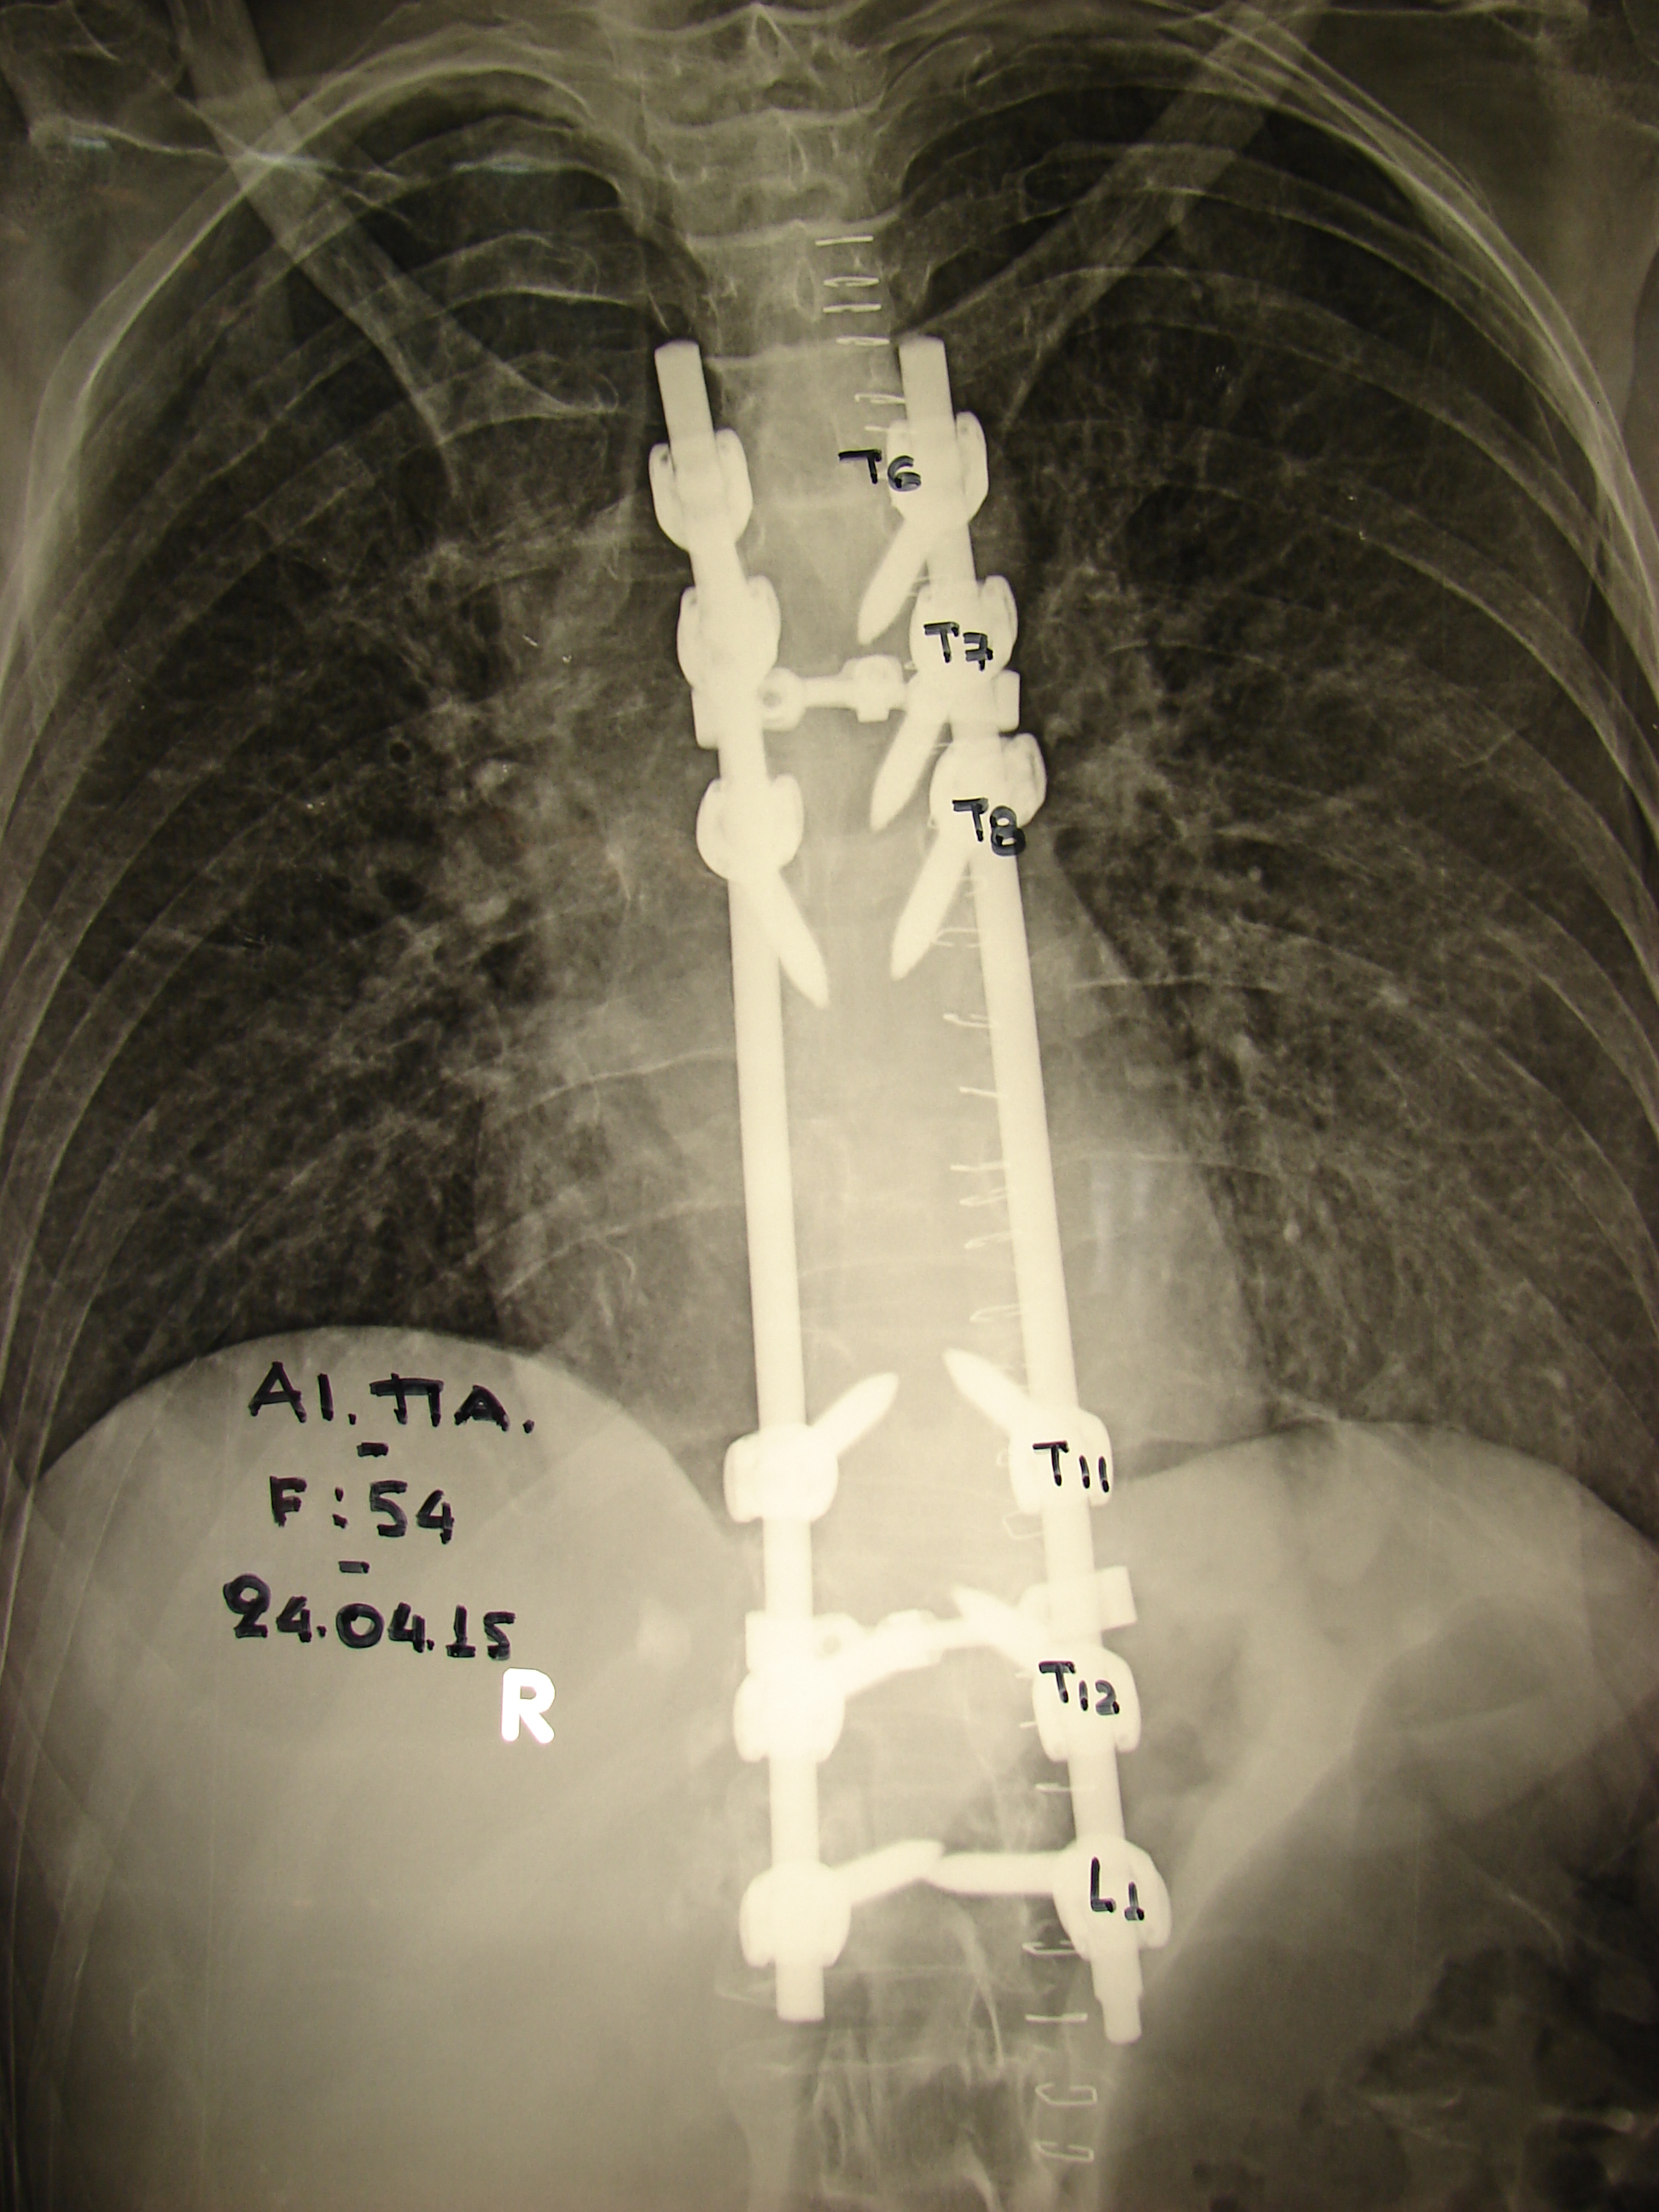

- α

- β

Εικόνα 5 α,β: Μετεγχειρητικές ακτινογραφίες α (προσθιοπίσθια) και β (πλαγία) της Θ.Μ.Σ.Σ.

Η μετεγχειρητική πορεία υπήρξε ομαλή και η ασθενής κινητοποιήθηκε σύντομα με τη βοήθεια βακτηριών βραχίονος – αντιβραχίου. Παρατηρήθηκε σημαντική βελτίωση της μυικής ισχύος των κάτω άκρων σε σύντομο χρονικό διάστημα μετά τη χειρουργική επέμβαση.

Η σταθεροποίηση της σπονδυλικής στήλης εγένετο με την εφαρμογή συστήματος σπονδυλοδεσίας. Οι διααυχενικές βίδες τοποθετήθηκαν σε τρία ακέραια επίπεδα, εκατέρωθεν των προσβεβλημένων 9ου και 10ου θωρακικού σπονδύλου.